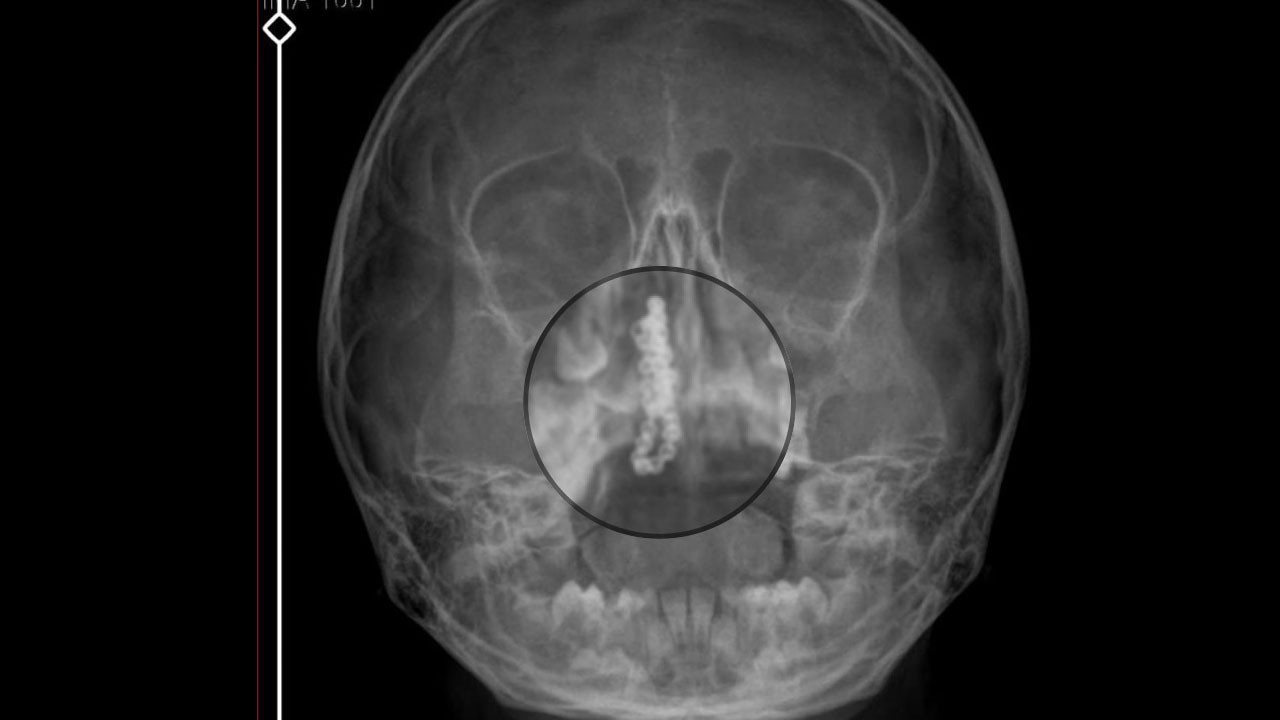

Toplantı kapsamında üç farklı rinoplasti ameliyatı canlı olarak gerçekleştirildi. Primer kadın rinoplasti, eğri ve deforme erkek rinoplasti ile zor bir revizyon rinoplasti operasyonları, konferans salonundan anlık olarak katılımcılara aktarıldı. Katılımcılar, ameliyat sürecini tüm detaylarıyla izleme ve teknikleri doğrudan öğrenme fırsatı buldu. Etkinlik boyunca rinoplasti alanında öne çıkan seçkin hekimler de deneyimlerini katılımcılarla paylaştı. Farklı vaka örnekleri üzerinden yapılan değerlendirmelerle, cerrahi teknikler ve hasta yönetimi konusunda önemli bilgiler aktarıldı.

Toplantının içeriğine ilişkin detayları paylaşan Prof. Dr. Soylu, “Organizasyonda canlı cerrahiler özellikle farklı hasta profillerini kapsayacak şekilde planlanıyor. Katılımcılar teorik bilginin ötesine geçerek ameliyat sürecini birebir izleme fırsatı buluyor.Her yıl olduğu gibi bu yıl da üç farklı cerrahi vaka planladık. Primer kadın rinoplasti, eğri ve deforme erkek rinoplasti ile zor bir revizyon rinoplasti operasyonları yapacağız. Bu üç farklı ameliyatın rinoplastinin önemli bir bölümünü kapsıyor. Canlı cerrahiler katılımcılara gerçek zamanlı öğrenme imkânı sunuyor” dedi.